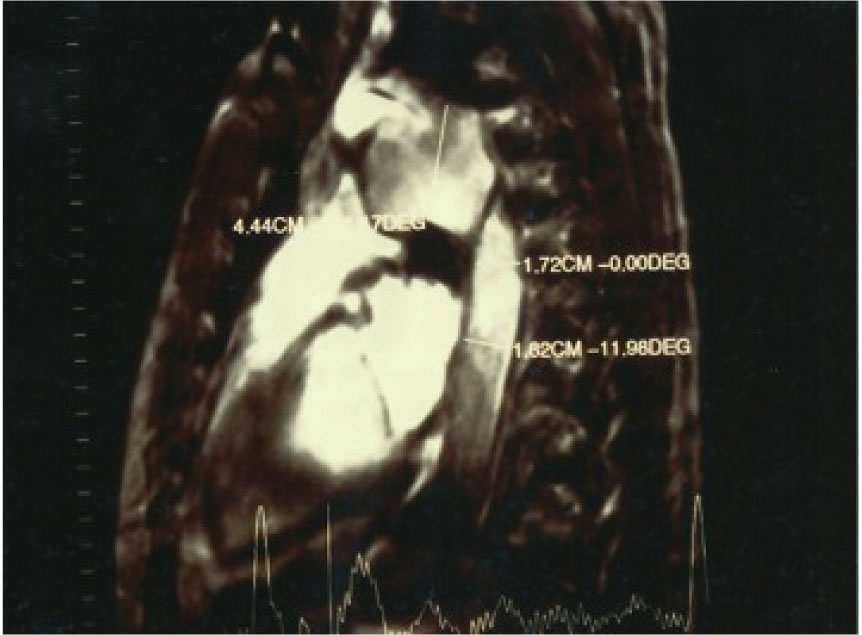

Fiber laryngoscopy showed an immobile left vocal cord in the paramedian position compatible with left recurrent laryngeal nerve paralysis. Further otolaryngological examination showed no abnormality. The laboratory findings were normal. In the potential suspect of an aortic injury, the patient underwent contrast material-enhanced spiral computer tomography (CT) of the chest. Moreover, because of its superior capability in depiction of functional information regarding flow patterns and luminal communications, MR imaging of the chest was also performed. At CT, MR and angioMR imaging a post-traumatic aortic pseudoaneurysm was revealed: concomitant compression of the left broncus was shown as well (Fig. 1, 2). The aortic pseudoaneurysm was consequently repaired by implantation of an endovascular stent graft under local anesthesia. The patient was discharged 10 days later, and at the 3-years follow-up visit the hoarseness and the dysphonia had resolved completely.

Angio MRI: Evidence of the relationship between the vascular intimal rupture post-traumatic descending thoracic aorta and the pseudo-aneurysm formation.